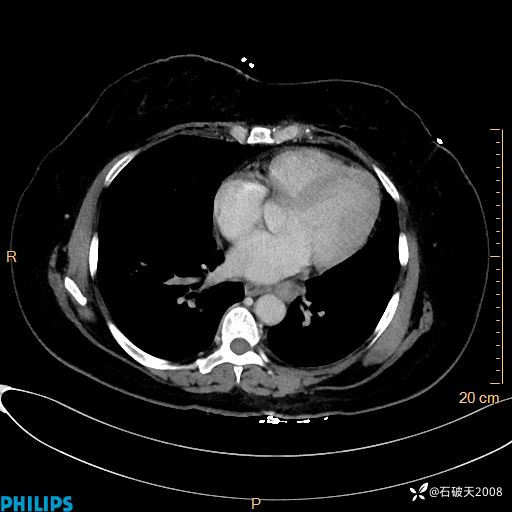

纵隔窗

动脉期